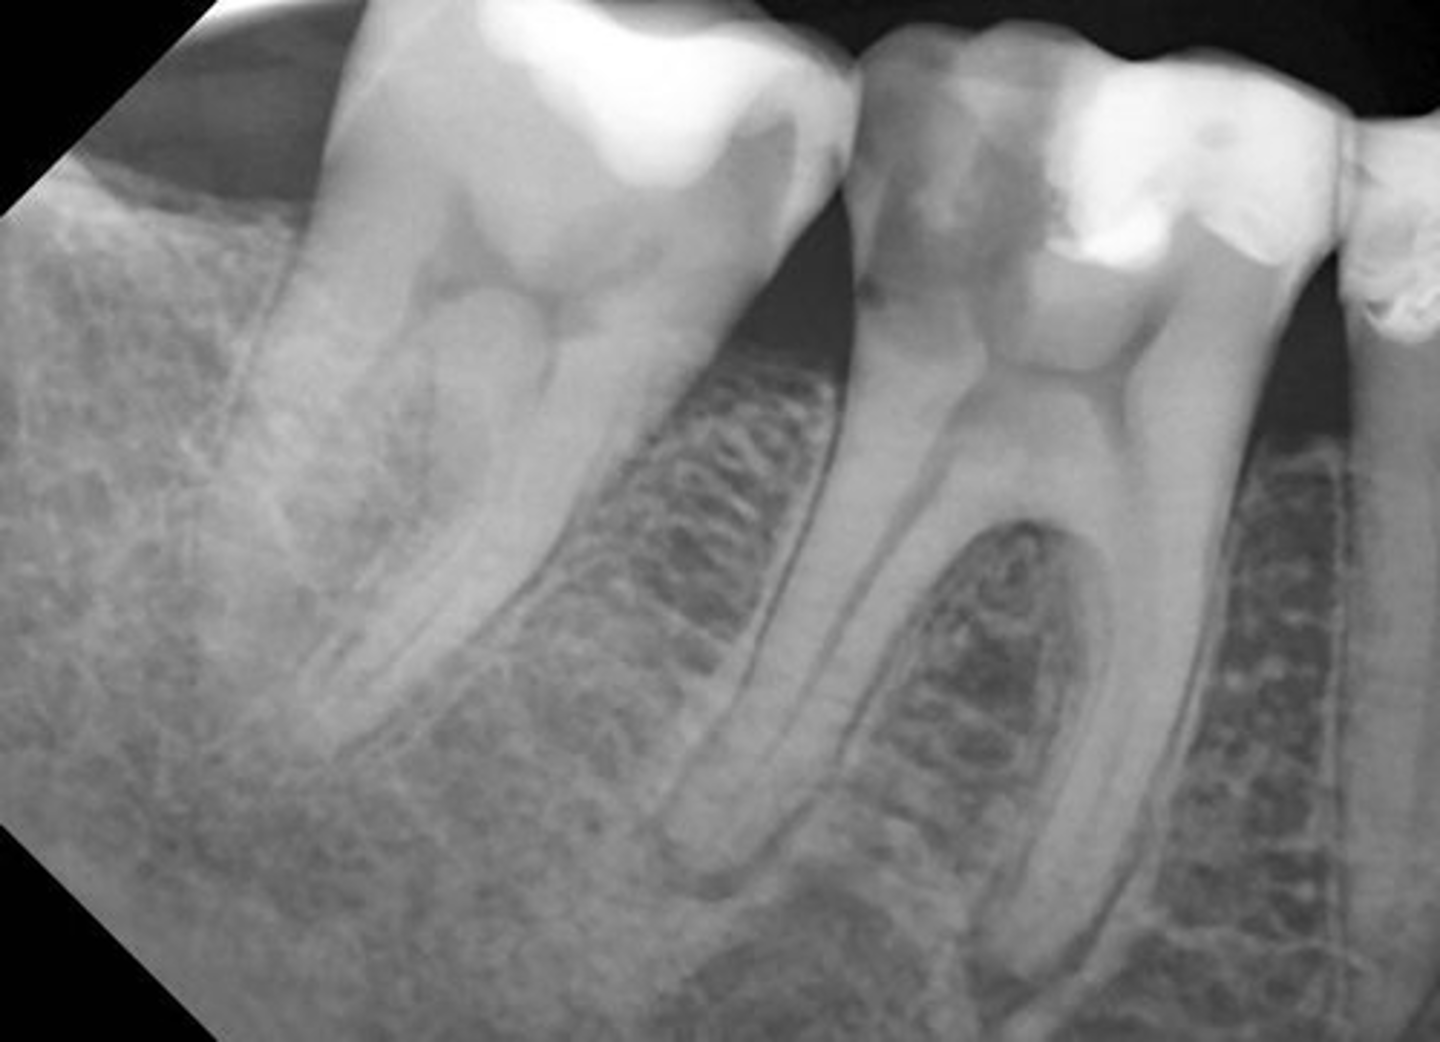

Radiographic features of apical periodontitis

widened PDL space

Thickening of the lamina dura

Radiographic features of Apical Rarefying Osteitis

radiolucent lesion

LOSS of lamina dura

margins either ill/well defined

corticated/non corticated

Radiographic features of Apical Sclerosing Osteitis

increased radiopacity

well-defined margins